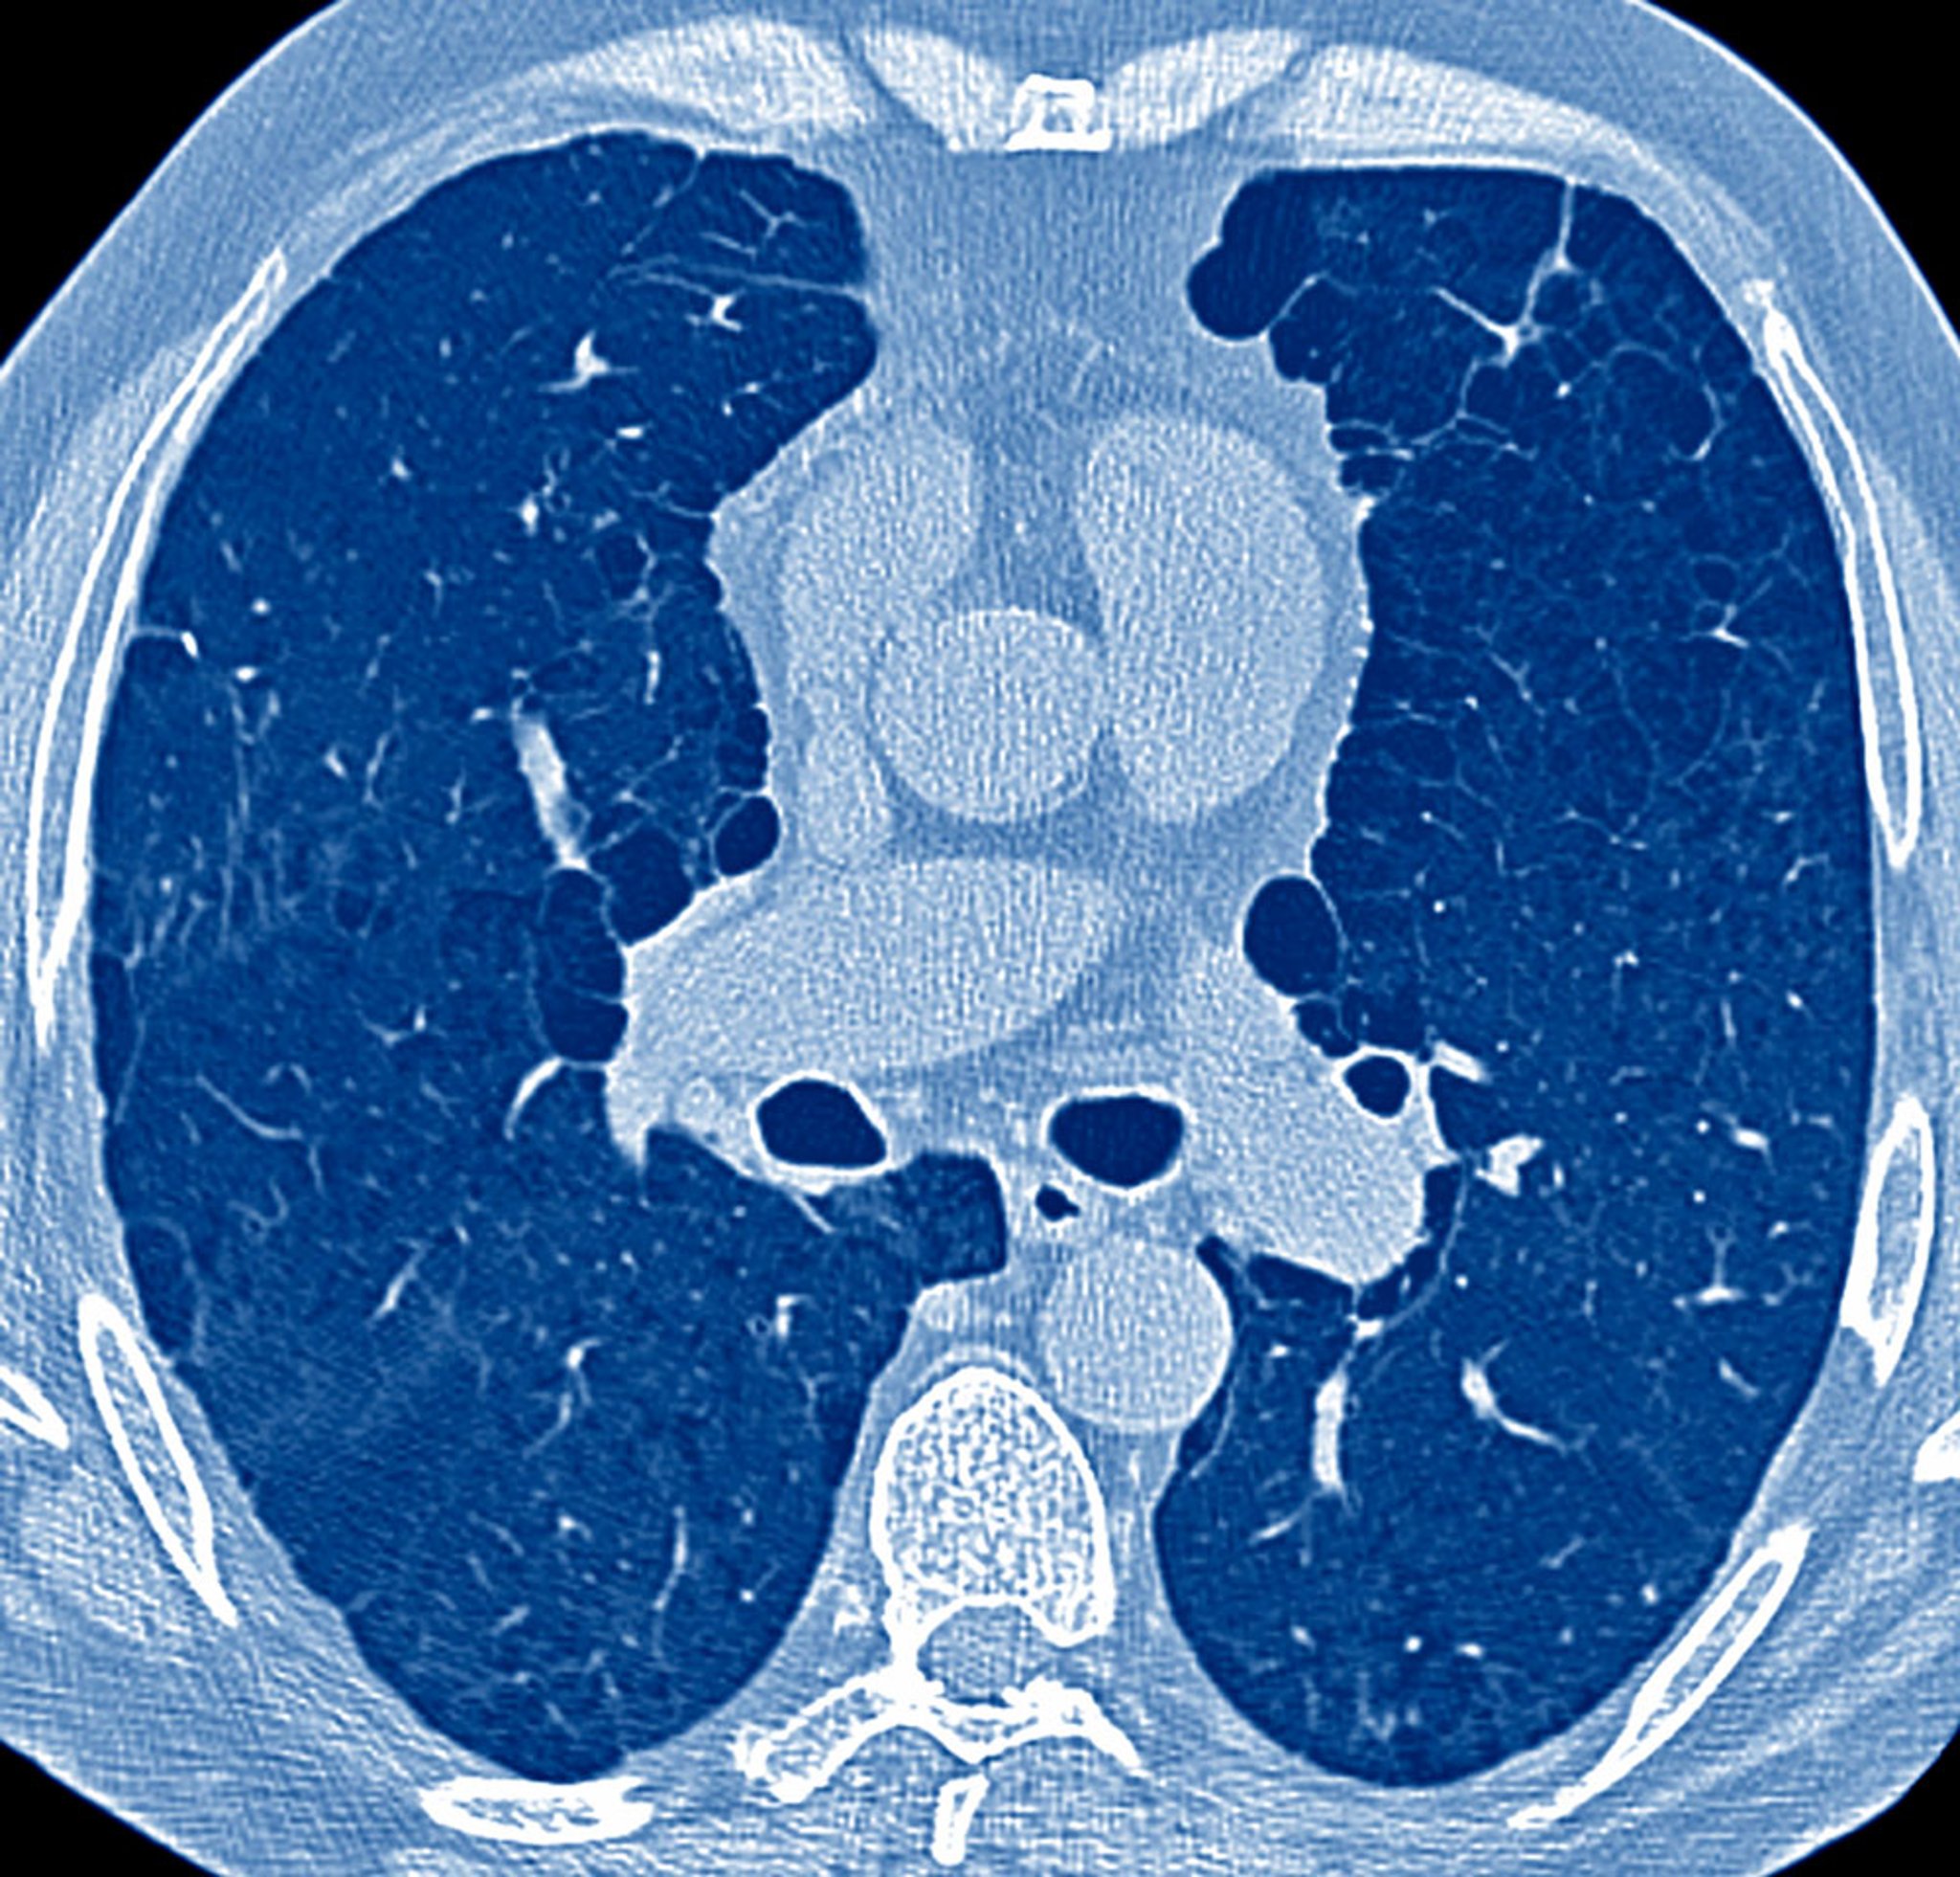

Los componentes fundamentales de los pacientes con síntomas pulmonares son los antecedentes, el examen físico y, en muchos casos, una radiografía de tórax. Estos elementos establecen la necesidad de realizar pruebas posteriores, que pueden incluir pruebas de función pulmonar, análisis de gases en sangre arterial, TC de tórax y otras pruebas de imagen torácica, ecocardiografía, prueba de marcha de 6 minutos, prueba de ejercicio cardiopulmonar, cateterismo cardiaco derecho, broncoscopia y biopsia pulmonar.